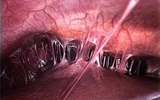

К чему приводят спайки? Опасны ли они? Брюшная полость устилается брюшиной, основные задачи которой кроются в обеспечении подвижности всех органов, сокращении их трения, сохранении жира в полости живота, защите от инфекции…